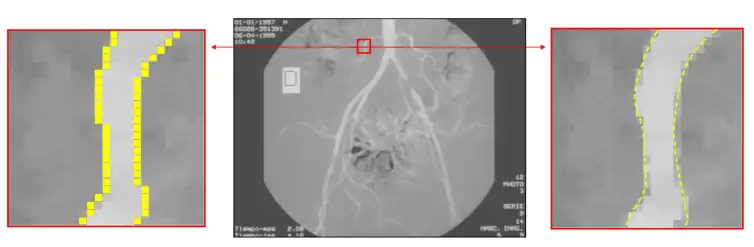

Subpixel

Edge detection on an angiographic image. On the left, edge detection is made at a pixel level. On the right, subpixel edge detection locates the edge inside the pixel precisely.